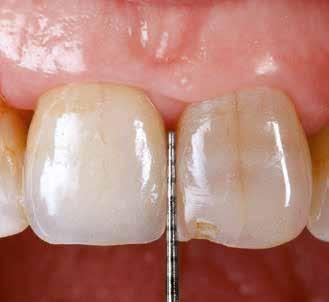

Az eljárást helyi érzéstelenítés mellett végeztük (4%-os articaine-hidroklorid 1:100 000 adrenalinnal). Papillakímélő, U alakú palatális bemetszést végeztünk, teljes vastagságú nyálkahártyalebeny preparálás történt, a lebenyt bukkálisan feltekertük (5. ábra). A lebeny bukkálisan feltekert részén de-epitelizációt végeztük el, amellyel kompenzálni tudtuk a bukkális lágyszöveti defektust. Szakaszos előfúrást végeztünk, és a bredent copaSKY 4x10 implantátumot 30 Ncm behajtási nyomatékkal helyeztük be (6. ábra). Az implantátumot 1 mm-re szubkresztálisan helyeztük be, hogy később szélesebb emergenciaprofilt tudjunk kialakítani (7. ábra). Az egyedi ínyformázó úgy készült, hogy kompozitot vittünk fel a titánbázisra, és így formáztuk a lágyszöveteket a transzgingivális gyógyulási fázis során (8. ábra). Az egyéni ínyformázó tulipán formájú, hogy kialakítsa a kívánt emergenciaprofilt. A lágyszövetet feszülésmentesen zártuk #6/0 nem felszívódó, monofil fonallal (Optilene, B. Braun Deutschland; 9. a–b. ábra). Posztoperatív röntgenfelvétel készült, ami alapján az implantátum a szomszédos fogakkal párhuzamos elhelyezést mutatott (10. ábra). Posztoperatív utasításokat adtunk a páciensnek a műtéti terület körüli szájhigiénia fenntartása érdekében. A beavatkozást követő egy héttel a varratokat eltávolítottuk, és a kezelt terület kielégítő gyógyulást mutatott (11. ábra). A 4 hónap utáni késleltetett terhelést a páciens kívánsága szerint terveztük.

A teljesen digitalizált protetikai munkafolyamat során az Exocad szoftver segítségével (exocad) egy hibrid, csavarrögzített, cirkónium monolit koronát gyártottunk le copaSKY

uni.fit titánalapra (bredent medical). Az implantátum körül a bukkális lágyszövet megfelelő vastagságot és kedvező ínykontúrt mutatott (12. a–b. ábra). Az egyedi ínyformázó eltávolítása után egészséges implantátum körüli lágyrészgallér

volt megfigyelhető (13–14. ábra), ezen kívül közvetlenül a műtét előtt intraorális vizsgálatot végeztünk a lágyszöveti profil megállapítása érdekében. Ezt követte a scanbody behelyezése, így digitális lenyomat készült az implantátum pozíciójáról (15. ábra). Ugyanezzel a technikával rögzítettük az antagonista fogívet és a harapást is. Az így kapott STL-fájlokat digitálisan továbbítottuk a fogtechnikai laboratóriumba. A titánalapra PMMA ideiglenes koronát készítettünk a proximális és marginális illeszkedés ellenőrzése érdekében, valamint a megfelelő harapás elérése céljából (16–17. ábra) Miután az összes igazítás elkészült, ismételt vizsgálatot végeztünk. A végleges hibrid csavarrögzítésű, teljes kontúrú cirkóniumkoronát titánalapon erősen polírozott szubgingivális résszel készítettük el, és 25 Ncm nyomatékra húztuk (18. ábra). Kiváló árnyalategyezést és klinikai eredményt